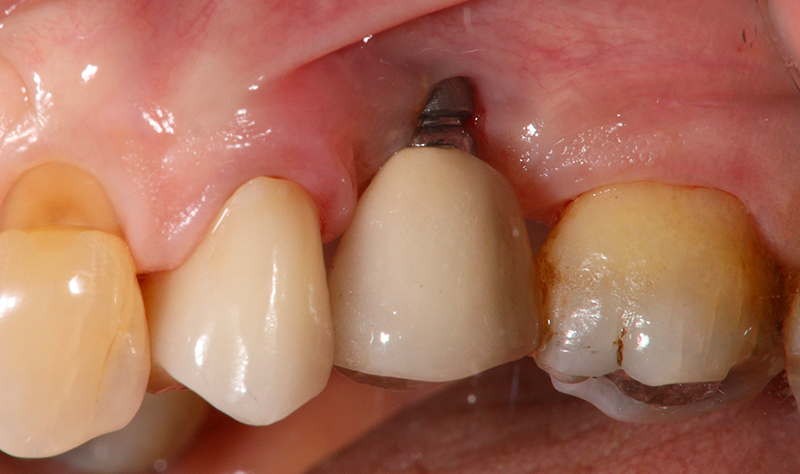

Dettaglio dell'elemento interessato da perimplantite

Fig. 2 - Dettaglio dell'elemento interessato da peri-implantite con evidente situazione clinica patologica.

Nell'ultimo anno le è stata riscontrata complicanza a carico dei tessuti peri-implantari di elemento zona 25. L'esame visivo e lo status fotografico (Figs. 1-2) evidenziano un’alterazione dello stato dei tessuti molli peri-implantari, che guida il clinico verso un’indagine più approfondita tramite acquisizione RX. Si esegue perciò esame radiografico del sito coinvolto (Fig. 3), da cui risulta un’importante riassorbimento osseo a carico dell’impianto. Si procede con sondaggio peri-implantare profondo, con la finalità di definire estensione e forma del difetto (Fig. 4) e, associandolo all’esame radiografico, di eseguire la conta delle spire implantari esposte. Tale manovra verrà effettuata con l’impiego di anestetico da irrigazione, data la nota dolorolabilità in peri-implantite, in quanto tale patologia determina la perdita di barriere connettivali e pertanto la penetrazione in osso durante il sondaggio.